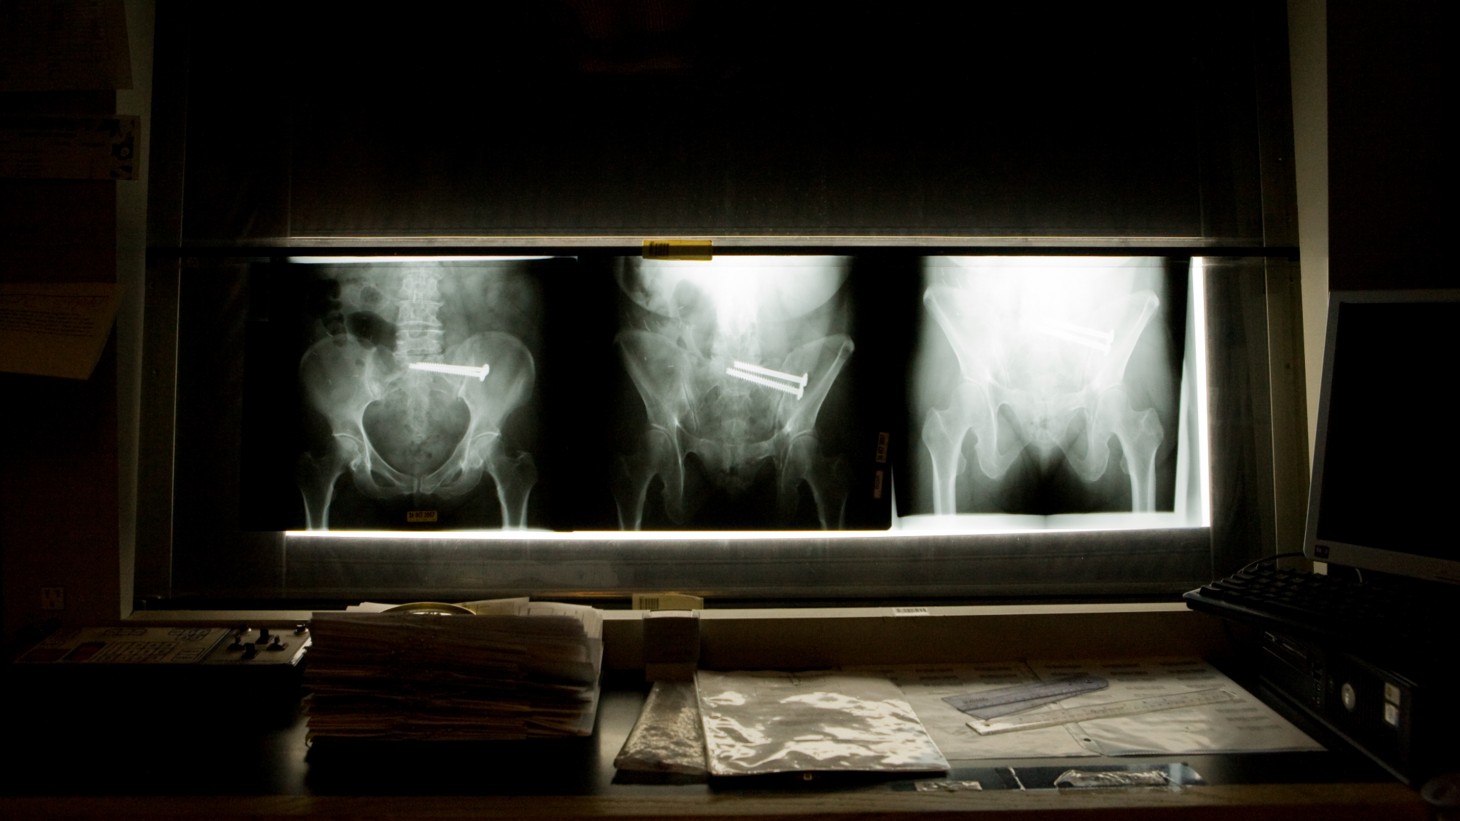

Alt text=” “

The diagnostic imaging department at the Woodland Hills Medical Center is improving workflow and boosting attendance by drawing on the wide experience of its team members.

• Team members in eight areas of expertise, including ultrasound, MRI, CAT scan, nuclear medicine, mammography, general x-ray, and special procedures.